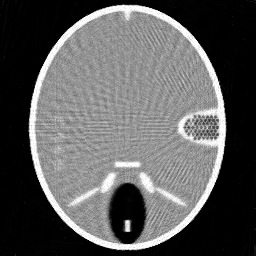

Figure 3. Results of different methods for reconstructing the head phantom with underdetermined rate 25% and relative noise level 0.8. (a) FBP (SNR=0.3505), (b) Landweber (SNR=0.1740), (c) Kaczmarz (SNR=0.1448), (d) L2-TV with scalar λ𝜆\lambda (SNR=0.1072), (e) Our method (SNR=0.0762), (f) λ𝜆\lambda in our method.

In Figure 2 and 3, we give the reconstruction results, which are shown in the same intensity range as the original phantom, from the simulated measurements with the noise level 0.2 and 0.8, respectively. Since the FBP algorithm is according to the analytical formulation of the inverse X-ray transform, it implicitly requires to have continuously measured clean data from the whole 0 to π𝜋\pi angular range. Therefore, it is not suited for reconstructing from noisy limited data. We can clearly see many stripe artifacts due to the noise and sparse projection angles in the FBP results. Both the Landweber and Kaczmarz’s methods perform better than FBP, but there are still some visible artifacts in the reconstruction. By using the TV regularization in the L2-TV and our methods, we potentially assume that the reconstructions are piecewise constant, which evidently reduces the influence of the noise and avoids stripe artifacts. In addition, comparing the results from the L2-TV and our methods, we find that our method suppresses artifacts much better while reconstructing most details. For instance, the grey region in the head and the black dotted region on the right side. With respect to SNR, it is also clear that our method gives the best reconstruction results. In Figure 2 (f) and Figure 3(f), we also plot the λ𝜆\lambda function obtained by our method. One can see that in the more textured regions λ𝜆\lambda is large in order to preserve the details, and in the more homogenous regions it is small to reduce artifacts.